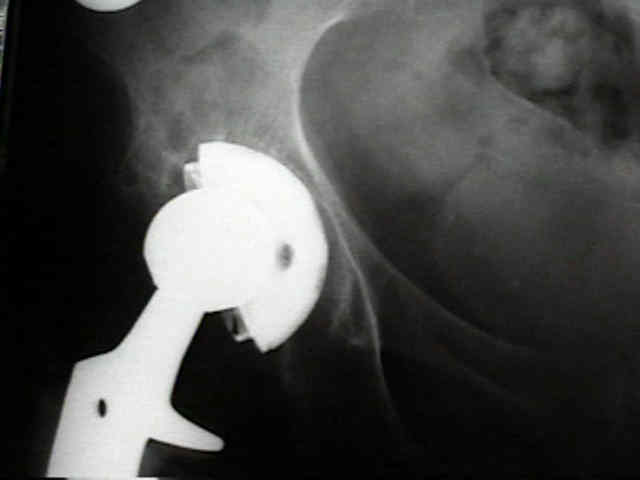

radiographic signs of ingrowth fixation

(from Moore MS, et al.)

- 97 percent of the cups with three or more of these signs were determined to be stable at the time of revision surgery

- in contrast, 83% of the cups with two or fewer signs were loose.

- five radiographic signs of stable cup fixation:

- absence of radiolucent lines

- presence of a superolateral buttress

- medial bone stress-shielding

- radial trabeculae

- inferomedial buttress